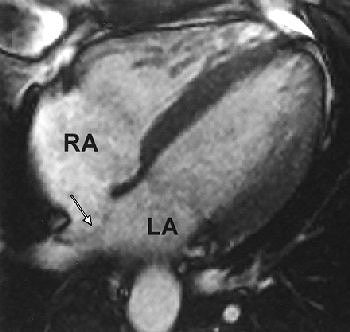

![]() |

| Thirty-two-year-old man with atrial septal aneurysm (arrow) on MRI. Typical bulging of atrial septum is shown toward left atrium in horizontal long axis (LA; RA = right atrium). Mohrs OK, Petersen SE, Erkapic D, Rubel C, Schräder R, Nowak B, Fach WA, Kauczor HU, Voigtlaender T, "Diagnosis of Patent Foramen Ovale Using Contrast-Enhanced Dynamic MRI: A Pilot Study" (AJR 2005; 184:234-240). |